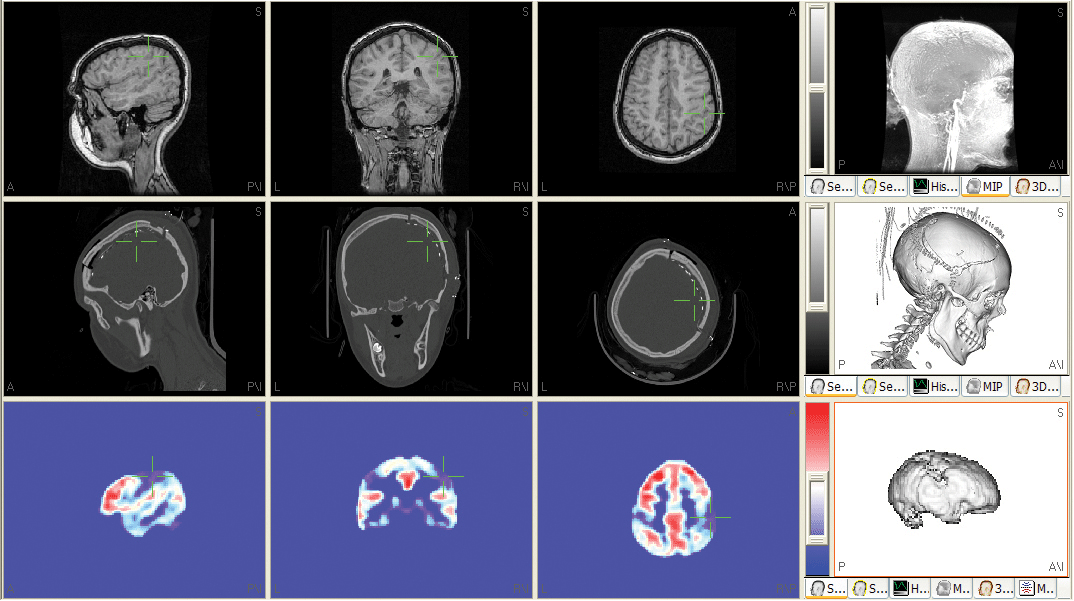

Automated 3D-co-registration using mutual volume gray-level matching

Largely improved co-registration accuracy can be achieved by this parameter-free, automated procedure. After setting the principal landmarks (Nasion and Pre-Auricular Points) in the first image modality (normally MRI), the algorithm is able to automatically co-register e.g. CT and / or PET images to this 'master' image dataset by optimizing the alignment by statistically analyzing the gray-level of all image data voxels.

Anatomical and functional atlases

Color-coded overlay and display of synonyms of different functional and anatomical atlases onto the structural image data.

Orthogonal cuts through segmented surfaces with volume image data display

3D-display of orthogonal cuts through segmented surfaces (skin or cortex) with overlay of definable image data sets.